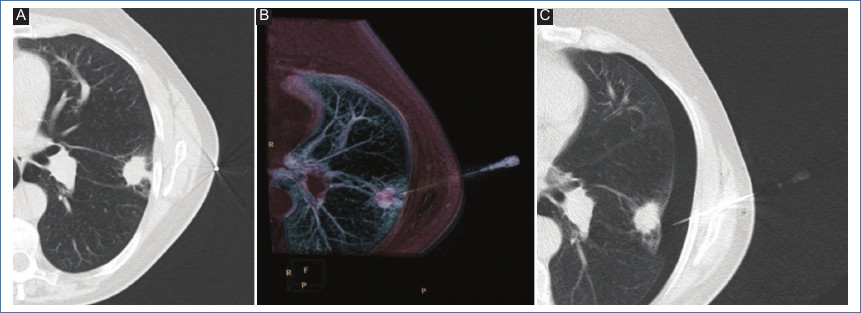

Las punciones fueron realizadas por un médico intervencionista entrenado con más de 10 años de experiencia en el campo. Se utilizó como método de elección la guía tomográfica, especialmente para aquellos pacientes que mostraron nódulos pulmonares solitarios no abordables por ecografía dado el tamaño tumoral, la interposición de parénquima pulmonar y la condición clínica del paciente debido al enfisema. Se seleccionaron también aquellos pacientes con nódulo pulmonar situado periféricamente, no abordable por vía transbronquial (Fig. 1 A)10.

Las biopsias se realizaron con aguja gruesa Tru-cut de 18 G, guiadas por TCMD (Phillips mx16EVO2), y se adquirieron imágenes de baja dosis de 120 kV/100 mA, con un espesor de corte de 3 mm y un intervalo de reconstrucción de 3 mm. Se realizaron en primera instancia imágenes de TCMD con un campo de exploración amplio con el fin de medir la lesión y elegir el sitio de punción. Previamente se colocó al paciente una guía metálica sobre la piel para determinar el punto de entrada de elección para la punción. El decúbito del paciente varió entre dorsal, supino y lateral respecto a la localización del nódulo y la elección del trayecto más apropiado. Luego, se esterilizó el plano cutáneo de la zona marcada con solución de povidona yodada, se colocaron campos estériles y se procedió a la aplicación de anestesia local, con infiltración del trayecto hasta la pleura con lidocaína al 2%. Todas las biopsias fueron realizadas con previa colocación de una aguja coaxial de 17 G en la dirección escogida, utilizando imágenes de TCMD seriadas durante el recorrido de la aguja para controlar el ángulo, la trayectoria y la profundidad de esta hasta alcanzar el nódulo que se deseaba biopsiar. En concordancia con la literatura, se dejó la aguja coaxial colocada en el interior de la lesión con el fin de entrar al parénquima pulmonar repetidas veces, con recolocación del estilete luego de cada muestra para evitar el ingreso repetido al parénquima, disminuyendo el tiempo del procedimiento, el daño de estructuras importantes y sus complicaciones11 (Fig. 1 B).

Un total de 14 (20%) pacientes desarrollaron neumotórax durante el procedimiento (Fig. 1 C). De ellos, 10 (71%) presentaron la complicación durante el retiro de la aguja coaxial y tres (21%) al momento del ingreso y ubicación de la aguja en el parénquima pulmonar. Dentro de estos últimos, al no poder alcanzar la toma de muestra, se consensuó con el equipo interdisciplinario para que luego de la mejoría clínica se realizara la biopsia en tiempo diferido.

Entre estos pacientes que desarrollaron neumotórax, 10 (71%) presentaban enfisema (RR: 4,0; IC95%: 1,411,4; p = 0,01), y de ellos, nueve (90%) desarrollaron el neumotórax al retirar la aguja coaxial.